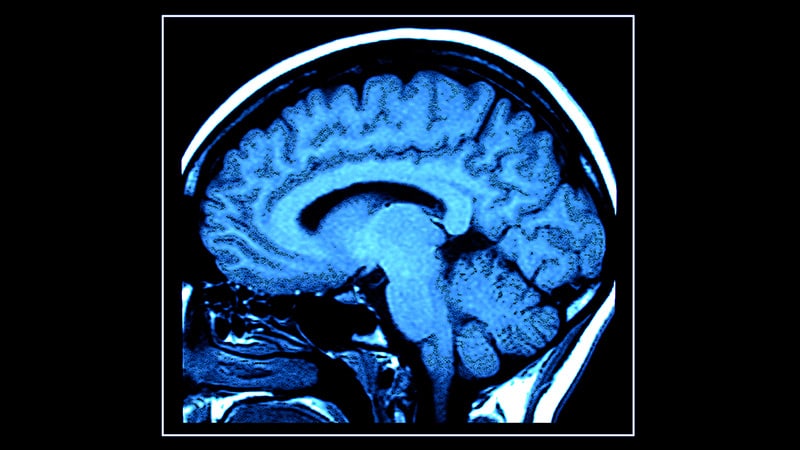

DURHAM,NC – A groundbreaking new method utilizing standard brain MRI scans can accurately assess a person’s biological age and predict their risk of cognitive decline,including dementia,researchers announced today. Dubbed “Dunedinpacni,” the tool offers a perhaps transformative approach to early detection and intervention in age-related neurological conditions.

Developed by a team at Duke University, building on decades of research from a long-term study in Dunedin, New Zealand, dunedinpacni bypasses the need for blood tests – a limitation of previous “aging clocks” based on DNA methylation analysis. The algorithm was trained using MRI data from 860 participants in the Dunedin study, analyzing 315 structural brain features, from cortical thickness to subcortical volumes.

The algorithm’s reliability has already been demonstrated across large, autonomous datasets, including the UK Biobank and the Latin American Brainlat dataset, accurately predicting cognitive impairments. Importantly, Dunedinpacni also reveals a strong correlation between socioeconomic factors and brain aging, showing that individuals with lower education levels or income tend to exhibit faster biological aging.Currently, Dunedinpacni provides a relative measure, comparing an individual’s aging speed to others within the Dunedin study cohort. However, researchers are rapidly working to establish standardized “norm tables” – similar to those used for height, weight, or BMI – to provide absolute age assessments.”We are confident that reference values will be available within the next year, making Dunedinpacni clinically usable within a few years,” says Hariri.

The potential applications are vast. Researchers envision dunedinpacni being used in clinical trials to assess the effectiveness of interventions aimed at slowing the aging process, and as a surrogate marker in Alzheimer’s therapies to determine if treatment is slowing disease progression, even in younger individuals. It could also refine study participant selection, ensuring more homogenous groups and minimizing risks associated with advanced aging.